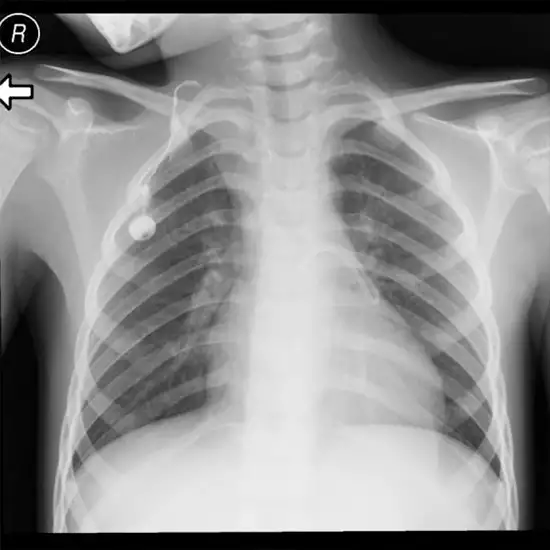

Contrast radiography is a standard technique that employs an opaque radiation substance, such as barium or iodine, as a contrast medium. The medium, which can be injected, eaten, or delivered through an enema, generates an image of the human body's interior.

Radiography with contrast can examine the appearance and function of interior structures.